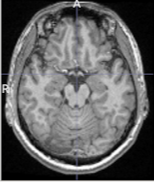

3D brain image에 대해 n4 bias field correction을 적용해보았을때의 모습이다(왼쪽 : original, 오른쪽 : processed). 자세히 살펴보면 original data에서의 low frequency를 갖는 region들이 향상이 된 부분을 볼 수 있다. (그림의 A 부분 참고)